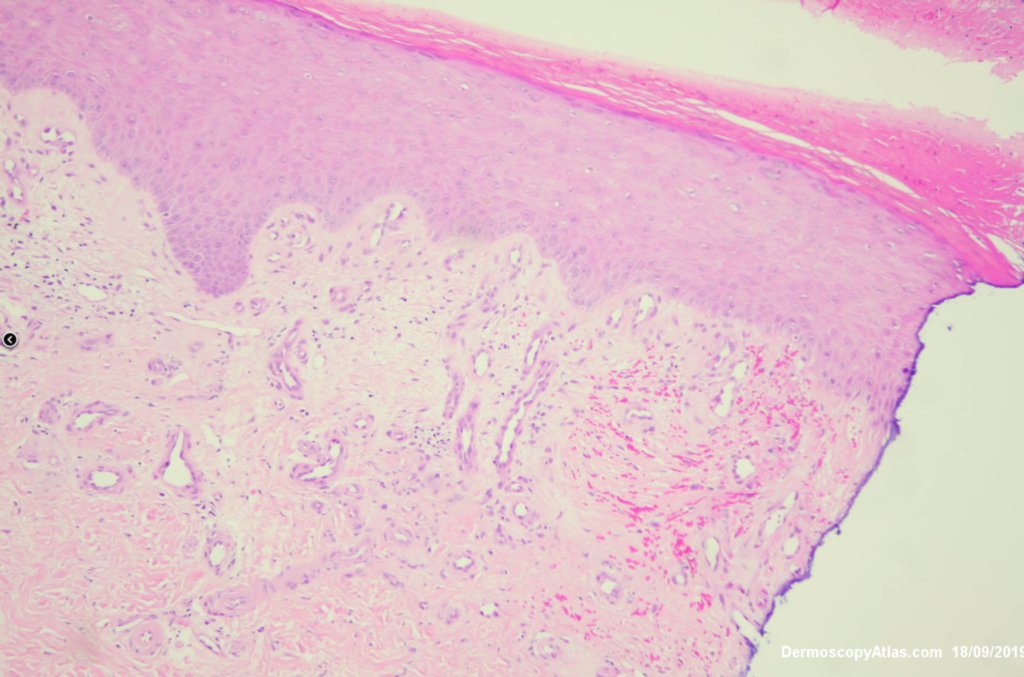

Diagnosis: Stasis vascular proliferation

Curious firm area on the heel that I thought was bleeding into a corn but there was stasis vascular proliferation in the dermis with some hemorrhage. I thought it might have been a talon noir or a wart but neither in the histology.